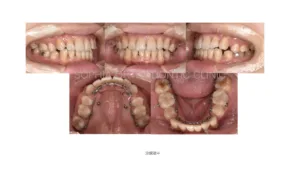

治療例(リンガル、ラビアル)

リンガル、前突.006